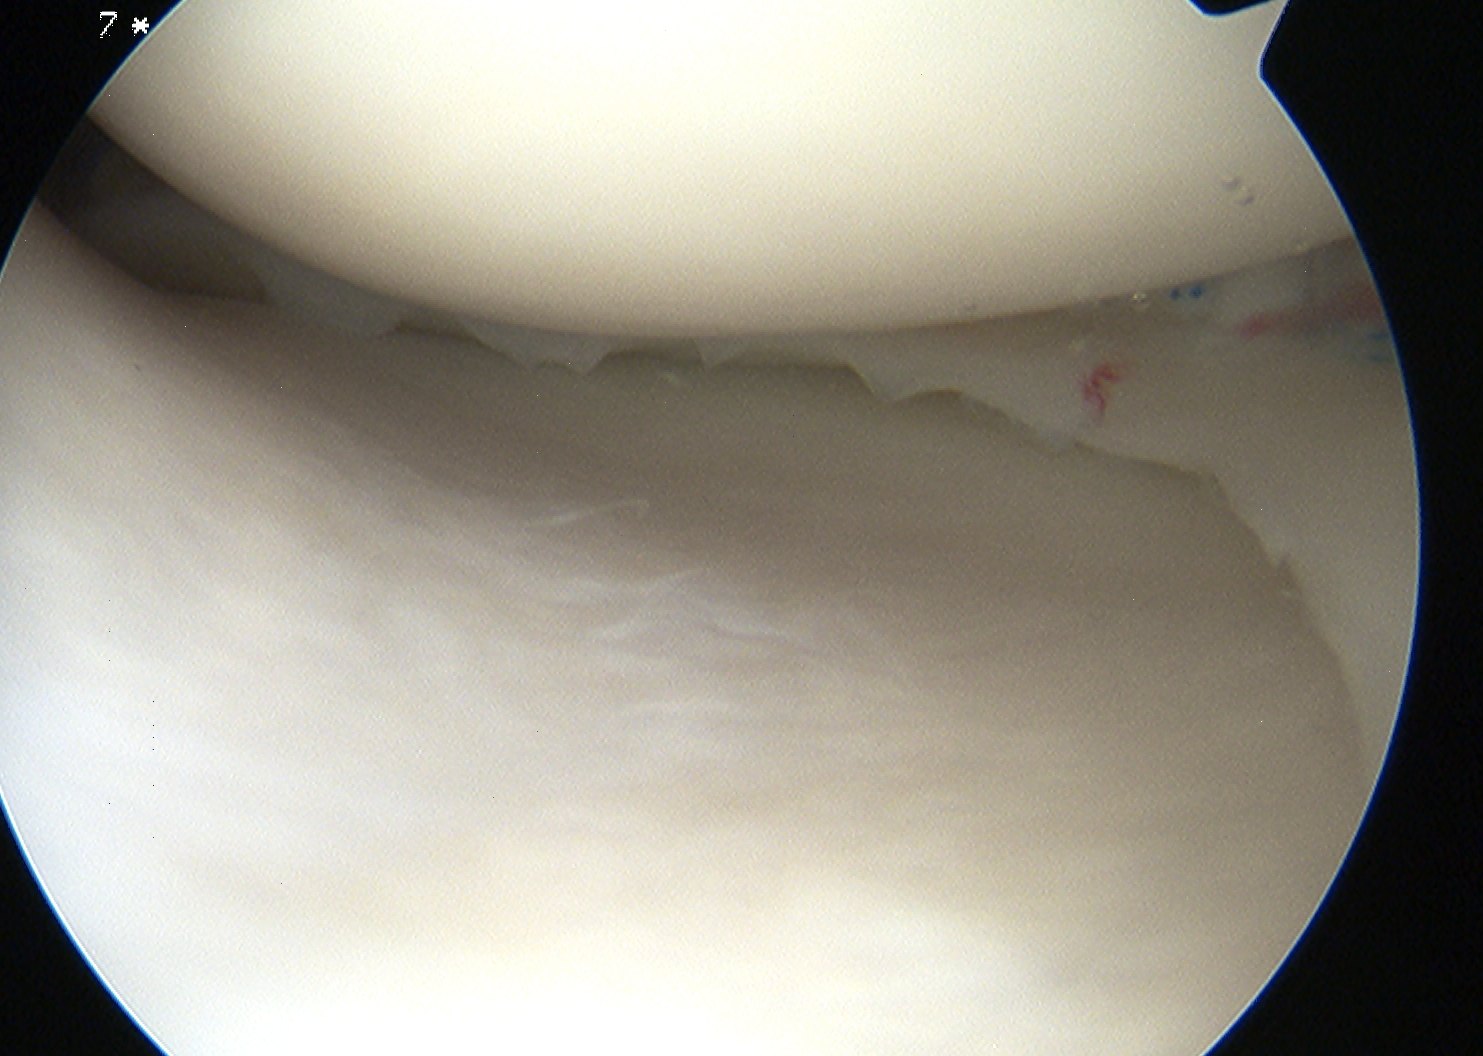

Ramp lesion